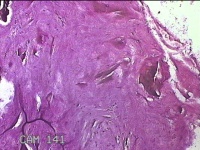

右侧中指指间关节背侧包块

性别

男

年龄

46岁

临床诊断

皮下结节

一般病史

发现右侧中指指间关节背侧一包块,伴间断性疼痛不适,考虑痛风结节。

标本名称

大体所见

灰白粉红色包块0.8x0.7x0.3cm一堆。